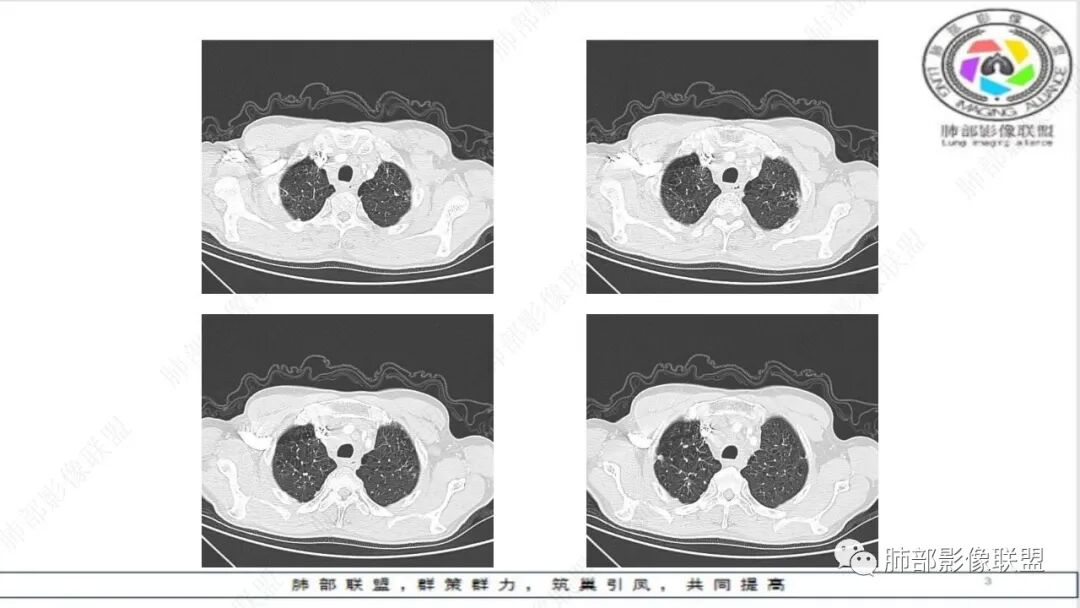

老年男性,肺气肿,左肺门及纵膈多发肿大淋巴结融合,包埋血管,冰冻,左肺上叶支气管受压变窄,左肺上叶胸膜下楔形实变,梗死灶?考虑小细胞癌,鉴别腺癌

晨读:老年男性,肺气肿背景,冰冻,血管挤压,恶,小,左肺胸膜下原发?肺栓塞?

冰冻纵隔,冰冻肺门,血管变细、变直,未见明显阻塞性肺炎,结合老年男性,考虑小细胞肺癌。

纵隔内及左肺门淋巴结肿大,冰冻纵膈,肺动脉包绕受压,支气管受压变窄,呈针孔样。双肺上叶结节及条索考虑陈旧结核。老年男性,慢支肺气肿背景,考虑小细胞肺癌。左肺上叶后段大片实变,不符合小细胞肺癌原发灶,二元论感染灶?肺栓塞?

晨读:男,65,咳喘1月余,加重3天。胸部CT:纵隔、肺门多发淋巴结肿大融合,冰冻纵隔,冰冻肺门,大血管包埋挤压,左肺A主干变窄。平扫密度较均匀,不均匀强化,灶性低密度。右上肺多发实性结节,中轴间质分布;左上叶针孔状支气管,后段胸膜下近楔形斑片影,融冰?考虑Ca,SCLC,并左上叶PTE?鉴别淋巴瘤。

纵隔及左肺门肿大、融合淋巴结,轻度不均匀强化,肺动脉、支气管包绕受压,左肺上叶叶间胸膜下条状实变,边界清,考虑小细胞肺癌

老年男性,肺气肿。影像:冰冻纵膈及肺门,大病灶内小灶状坏死,少部分病灶明显坏死,肺动脉包绕受压,支气管受压变窄,呈针孔样改变。考虑小细胞肺癌,鉴别淋巴瘤,转移瘤。

晨读,老年男性,肺气肿背景,左肺门及纵隔内多发肿大淋巴结,部分融合、包埋血管,冰冻状,左肺上叶支气管受压变窄。双肺散在小结节,左肺上叶胸膜下楔形实变。考虑恶性病变,小细胞肺癌,鉴别淋巴瘤、转移瘤

老年慢性,肺气肿背景,纵隔左肺门明显多发肿大淋巴结且融合,密度相对均匀,增强后轻中度强化,偏纵隔右侧淋巴结坏死明显,左肺支气管可见受压变窄,呈针孔样改变。左肺上叶叶间裂上方山丘状混合磨玻璃病灶,内密度不均可见空泡。考虑小细胞肺癌(娘小崽大)。

老年男性,肺气肿背景,左肺上叶后段斑块病灶,边缘清膨隆感,有强化,蜂窝状破坏,胸膜下载赃,纵隔及左肺门多发淋巴结肿大及强化,部分坏死,融合呈大团块,左主支气管外压变窄,并包埋左肺动脉受压,方向左肺上叶后段低分压腺ca并左肺门及纵隔淋巴结转移肿大,右肺上叶转移结节,建议超声支气管镜,左肺门淋巴结活检。

老年男性,娘小崽大,冰冻纵膈,小山丘征,支持恶性肿瘤中小细胞肺癌。

冰冻肺门,冰冻纵隔,肺A包绕受压,针孔样支气管,典型小细胞癌

联盟晨读病例:左肺门软组织肿块,纵隔淋巴结肿大相互融合,左肺上叶支气管狭窄,血管受压,左肺上叶阻塞性肺炎,考虑左肺上叶中心型肺癌伴纵隔淋巴结肿大,左肺上叶阻塞性肺炎。小细胞癌。